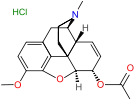

Structures

| Morphides | ||||

|---|---|---|---|---|

Codeine Codeine |

Morphine Morphine |

Oripavine Oripavine |

Pseudomorphine Pseudomorphine |

Thebaine Thebaine |